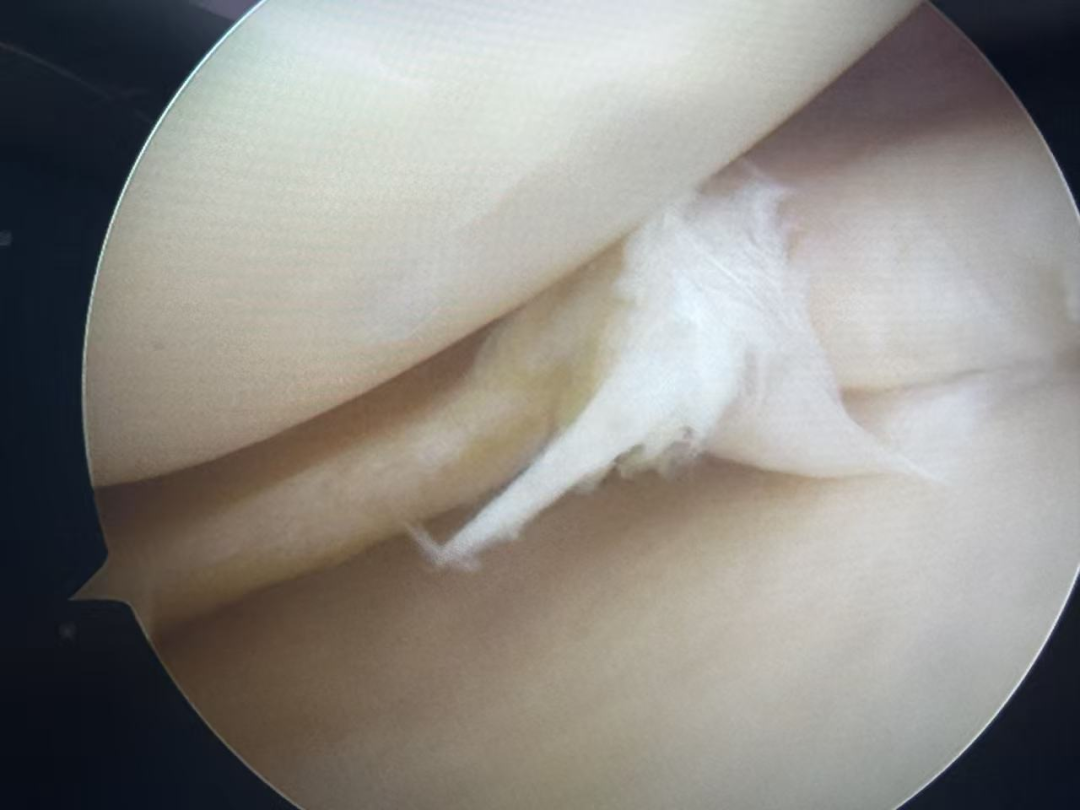

术中镜下探查清晰发现,患者膝内侧半月板体部下层撕裂,「隐藏」在上层下方,正是这一隐匿损伤给磁共振检查「蒙上了一层面纱」,这一发现无疑是「拨开云雾见晴天」,所有疑惑迎刃而解。